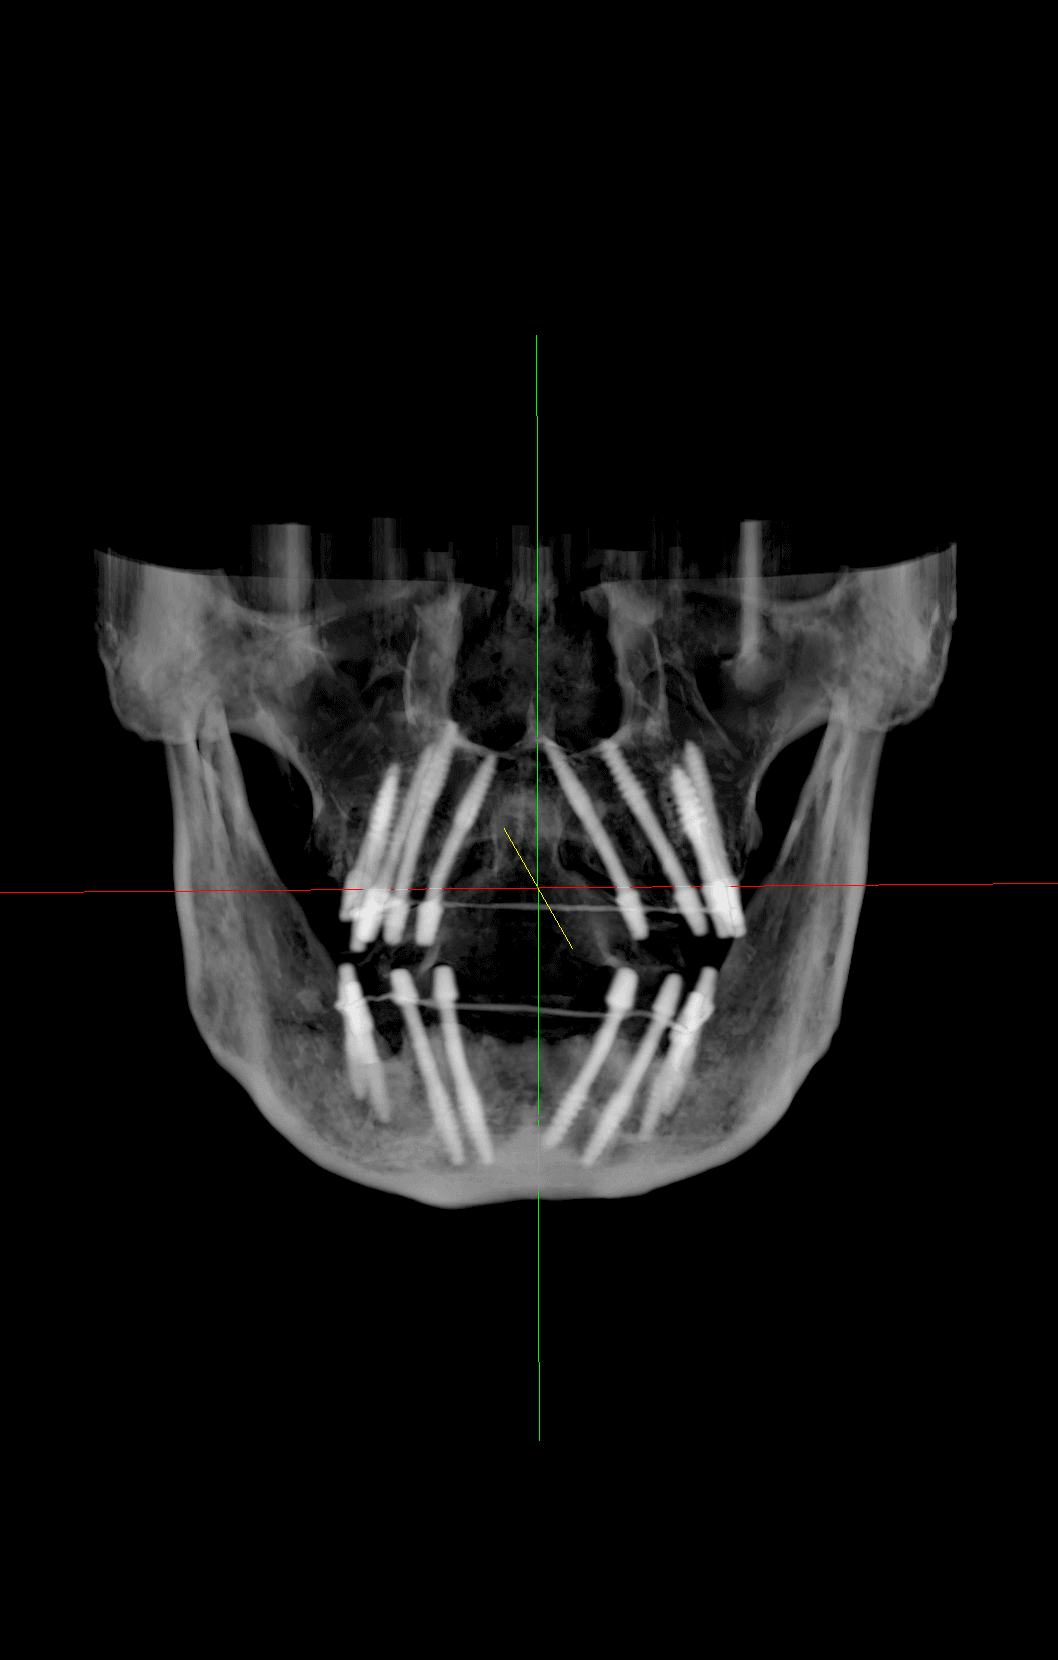

Bi-cortical Engagement

Master the art of bicortical engagement for unmatched implant stability. Learn advanced corticobasal techniques, including nerve bypass, ensuring immediate loading and longterm success.

Nerve bypass is an important technique to rehabilitate the posterior mandible without risking inferior alveolar nerve injury. It allows placement of implants in severely resorbed jaws while avoiding neurosensory complications.